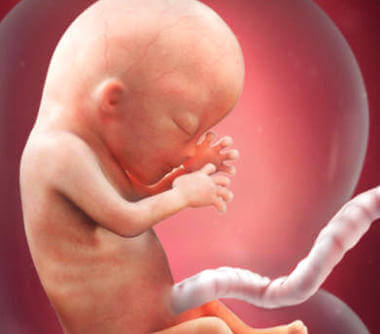

Un nouveau trimestre commence. C’est aussi une nouvelle étape du processus de gestation de cette petite créature qui vit dans votre utérus. En cette 13ème semaine de grossesse, sa taille est comprise entre 6,5 et 10 centimètres et son poids varie de 13 à 20 grammes. Son visage commence à former ses caractéristiques particulières, parmi d’autres transformations que nous vous donnons ci-dessous. C’est incroyablement excitant !

En plus de l’emplacement final de ses yeux (auparavant, ils étaient éloignés l’un de l’autre) et ses oreilles, qui se sont placées la semaine précédente où elles resteront pour la vie (avant, elles étaient plus en arrière), il y a un détail vraiment fascinant. Ses empreintes digitales sont déjà là.

Le cerveau est l’une des parties les plus développées du fœtus. Il en est de même des structures qui supportent et recouvrent les organes. Par conséquent, la tête représente pour l’instant la moitié de la taille totale du fœtus.

A partir de maintenant, le corps commencera à croître plus rapidement pour “la rattraper” et ainsi atteindre un corps proportionné. En effet, à la naissance, la tête ne représente qu’un quart de la taille totale. En outre, il y a aussi quelques processus très importants liés à l’organisme du fœtus et à sa mise en œuvre.